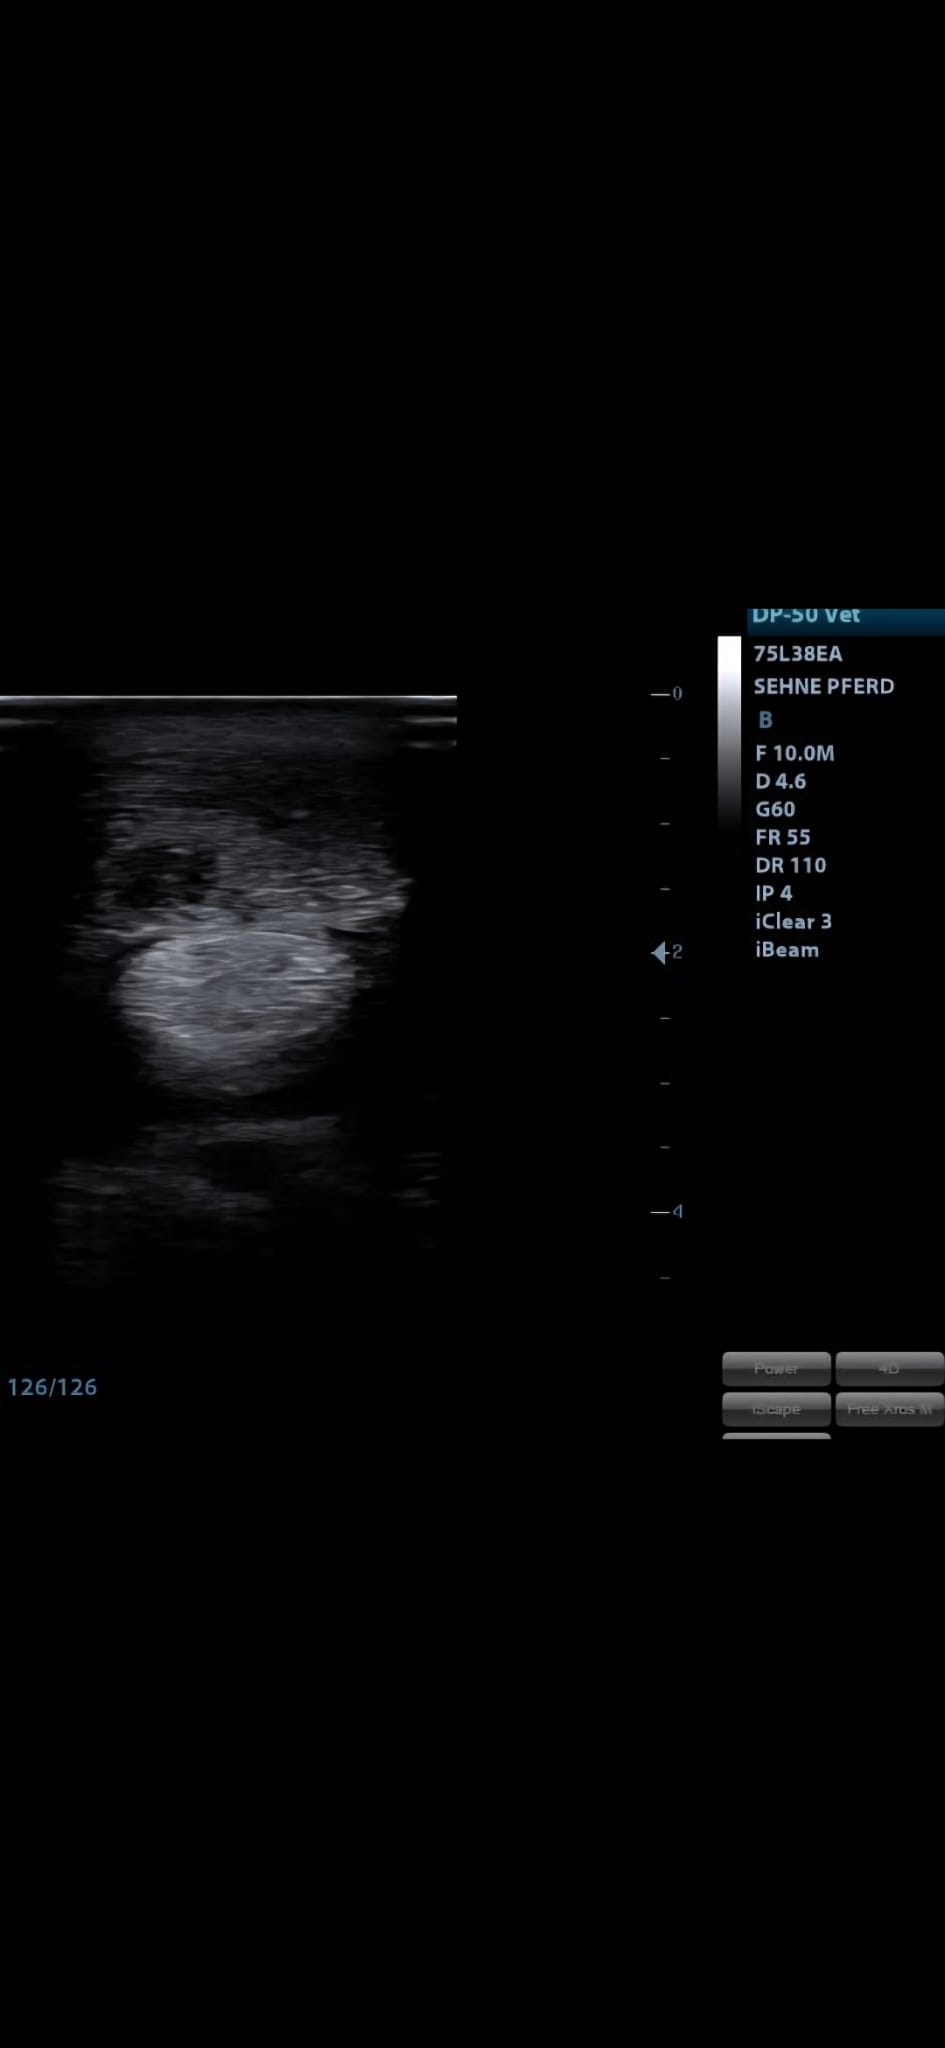

Bildgebende Diagnostik mittels modernster Ultraschalltechnik.

Ob Pferdemedizin mit Schwerpunkten in Orthopädie, Innere Medizin und Turnierbetreuung oder Kleintierpraxis mit modernster Ultraschalldiagnostik und Weichteilchirurgie — bei mir ist Ihr Tier in besten Händen.

Ultraschall, Labordiagnostik und bildgebende Verfahren ermöglichen uns eine schnelle und präzise Diagnose für Ihr Tier.